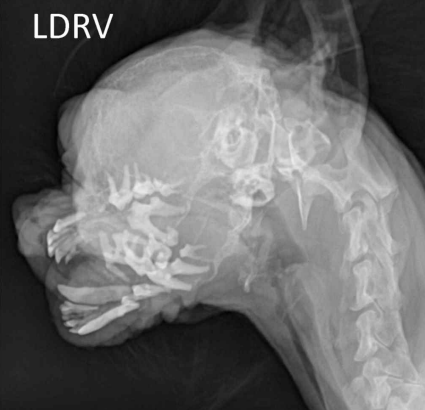

| Renal osteodystrophy (์ ์ฑ ๊ณจ์ดํ์ฑ) | - ๋ผ์์ ์นผ์์ด ๊ณผ๋ํ๊ฒ ๋น ์ ธ๋์ ๊ณจ๋ฐ๋ ๊ฐ์ - ์ฑ์ฅ๊ธฐ(6-12๊ฐ์) โ ์คํ๋ ค ๋ผ ๋๊บผ์์ง ์ ์์ - ๋ ธ๋ น, CKD โ Rubber jaw : ์ฝ๊ฐ ๊ณ ๋ฌด์ฒ๋ผ ๋ฌผ๋ ํด์ง |

![]() | - ์์ , ํ์ , ์น์ฃผ๊ณจ์์ ์นผ์ ๊ฐ์, ๋ผ ๋ฐ๋ ๊ฐ์ |

| | - ์ ์ฅ ๊ธฐ๋ฅ ์ ํ |

ํ์ ๋ผ ์์ค, ์ด๋นจ ์์ค, ์ฒ์ถ ๋ผ ๋ฐ๋ ๊ฐ์,

ํ์

๋ผ ์์ค, ์ด๋นจ ์์ค, ์ฒ์ถ ๋ผ ๋ฐ๋ ๊ฐ์,